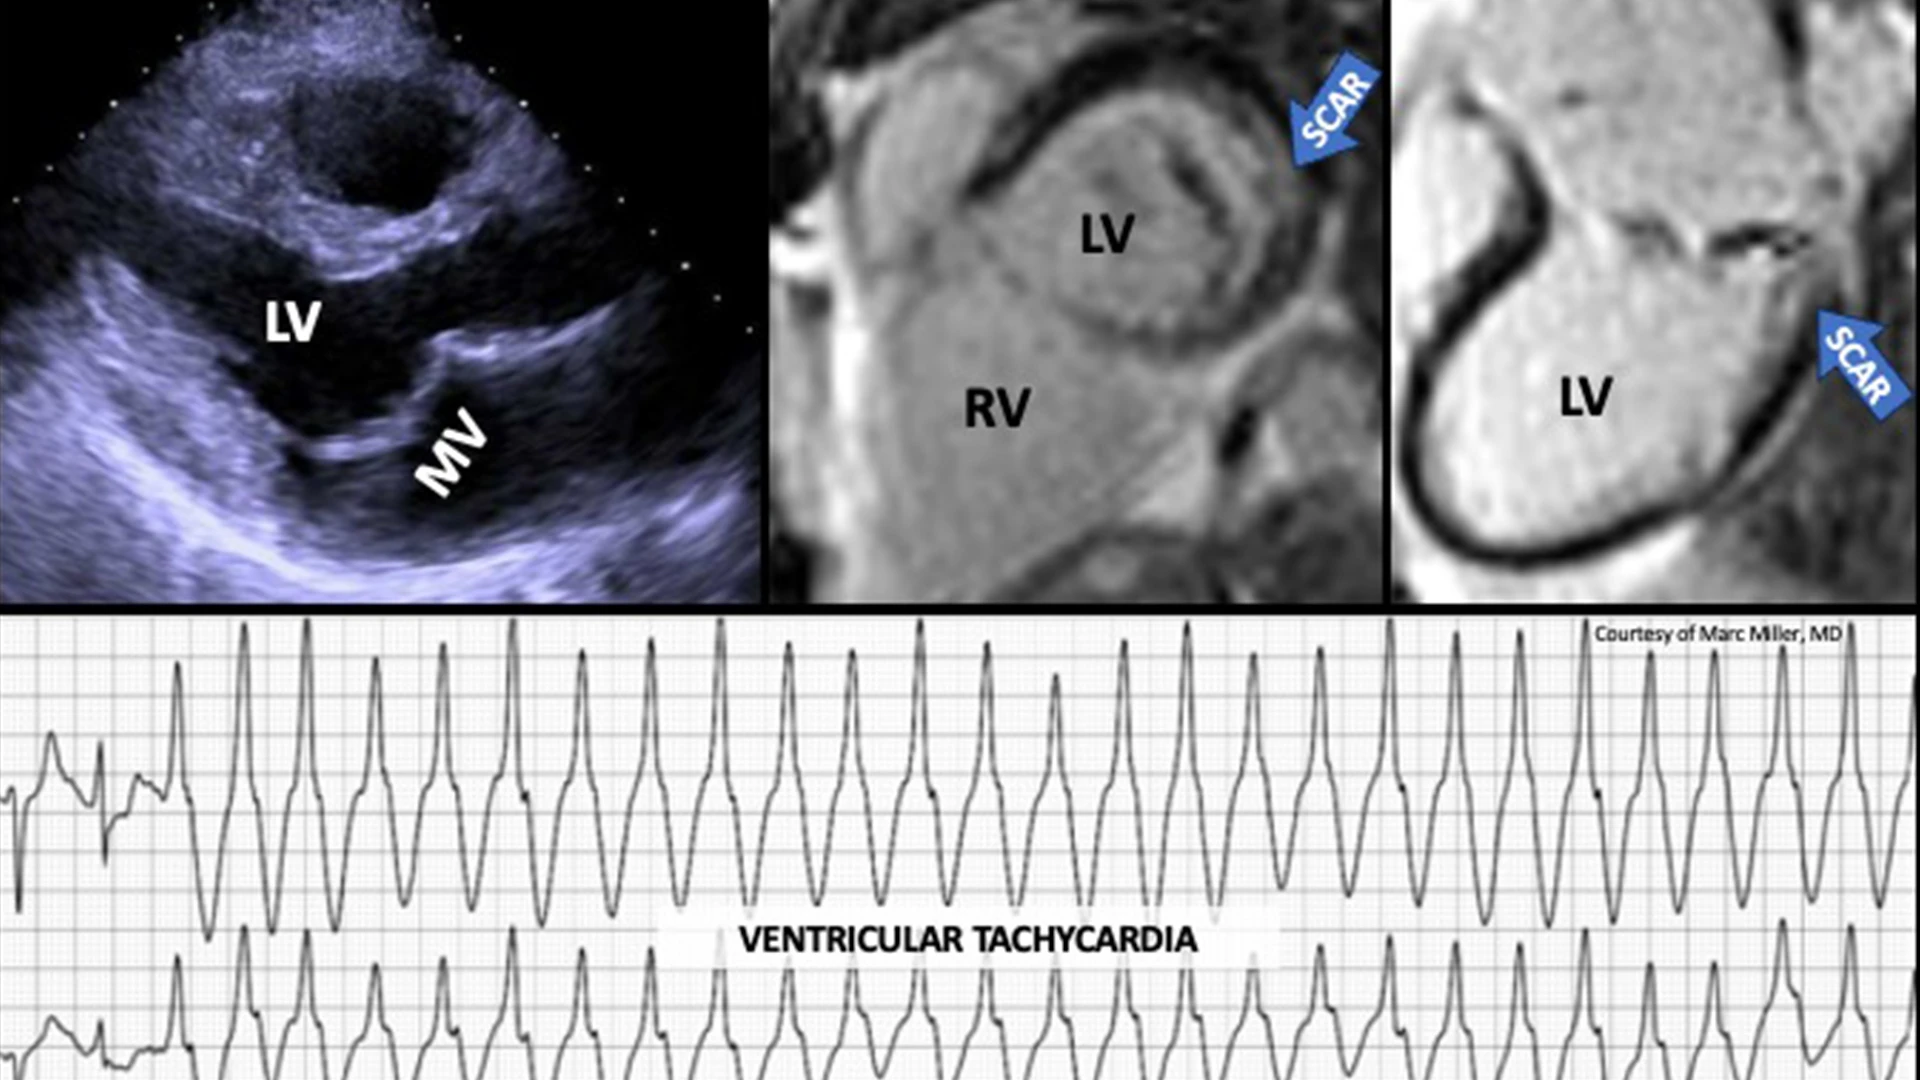

Images were obtained from a man in his mid-50s with asymptomatic degenerative mitral valve prolapse (bi-leaflet) with mild-moderate mitral regurgitation, who had an episode of syncope without prodrome. A subsequent ambulatory ECG monitor was notable for frequent salvos of ventricular tachycardia. Cardiac MRI imaging demonstrated replacement fibrosis (scar) in the basal infero-lateral left ventricle.